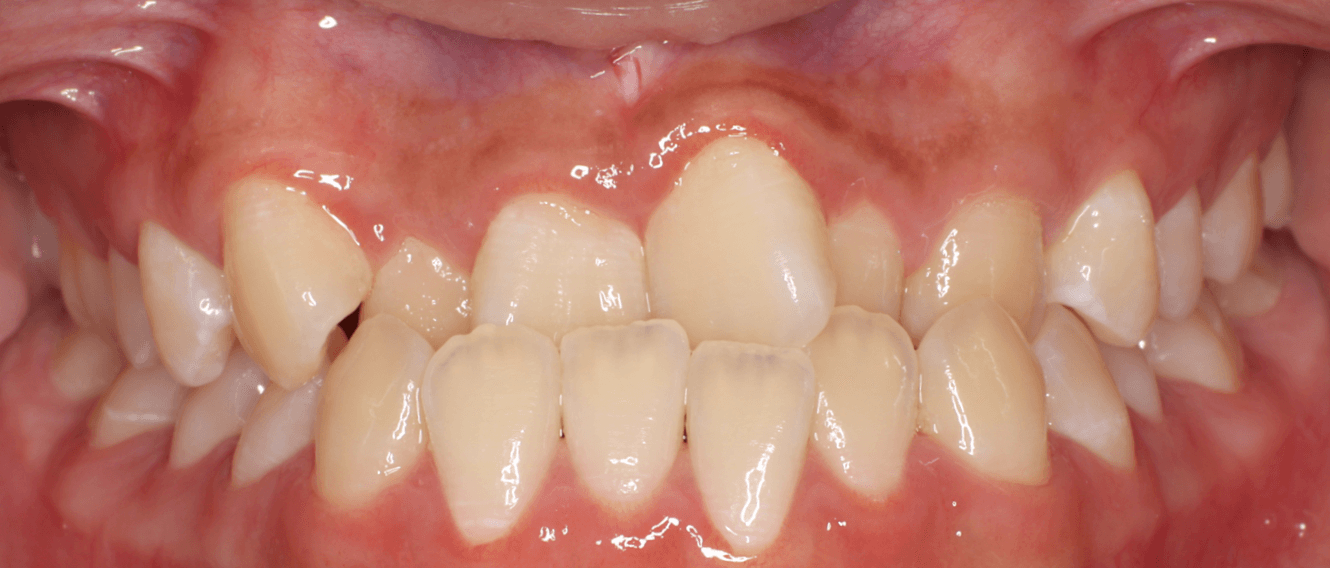

反対咬合の症状の重さを見るポイントとしては、「切端咬合位」「下の前歯の不ぞろい」「下あごの左右差」をみていきます。

切端咬合位が取れるか

反対咬合は、前歯の位置異常が原因の場合は軽度であり、骨格の不調和が原因の場合は重度であることが多くなります。そこで受け口の治療難易度を調べる上で、上下の前歯を歯先で合わせる「切端咬合位」ができるかが重要な指標となります。

切端咬合位ができる反対咬合は、早期接触といって上下の歯をかみ合わせた際に奥歯より前歯が先に接触していしまうため、下あごを前に出てしまい受け口となってしまうメカニズムです。機能性反対咬合とも呼びます。

この場合は、前歯の位置以上が原因となっているため、準備矯正治療で前歯を移動させることで受け口の改善は可能です。奥歯が永久歯に生えかわる前に早期に矯正治療を開始することをお勧めいたします。

一方、どんなにあごを動かしても切端咬合ができないは、上下あご骨の長さの違いが原因となっている可能性があり難易度が高まります。レントゲン分析で下顎の相対的な長さを計測し、治療成功率を算出します。

下の前歯のがたつきの様子

下の前歯の歯並びが前後的に乱れているだけなら、マウスピース装置で内側に傾けることで改善できますが、下の前歯にねじれや傾きの問題がある場合は、スペース不足が大きく、内側への移動が難しくなるため難易度が高まります。

そうすると、下の前歯にすき間がある受け口の方が治療は有利となります。